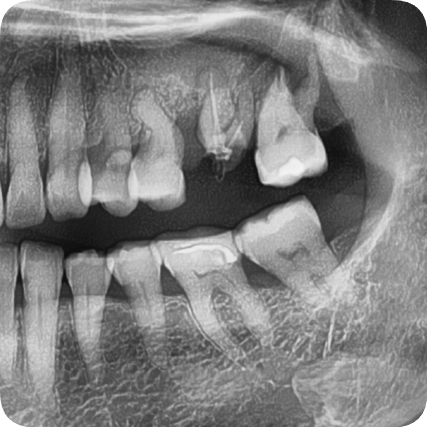

At the first visit

At Seoul Orbit Dental Hospital, we take a 3D CT scan before all implant treatments.

In this case, we found:

-

Severe bone loss around #26 and #27

The maxillary sinus had descended significantly

Inflammation between the root and the gum

Based on the panoramic X-ray and intraoral photos,

we diagnosed the following:

The two upper left molars were fractured and missing

The surrounding alveolar bone was relatively healthy, so implant placement was possible with minimal bone grafting